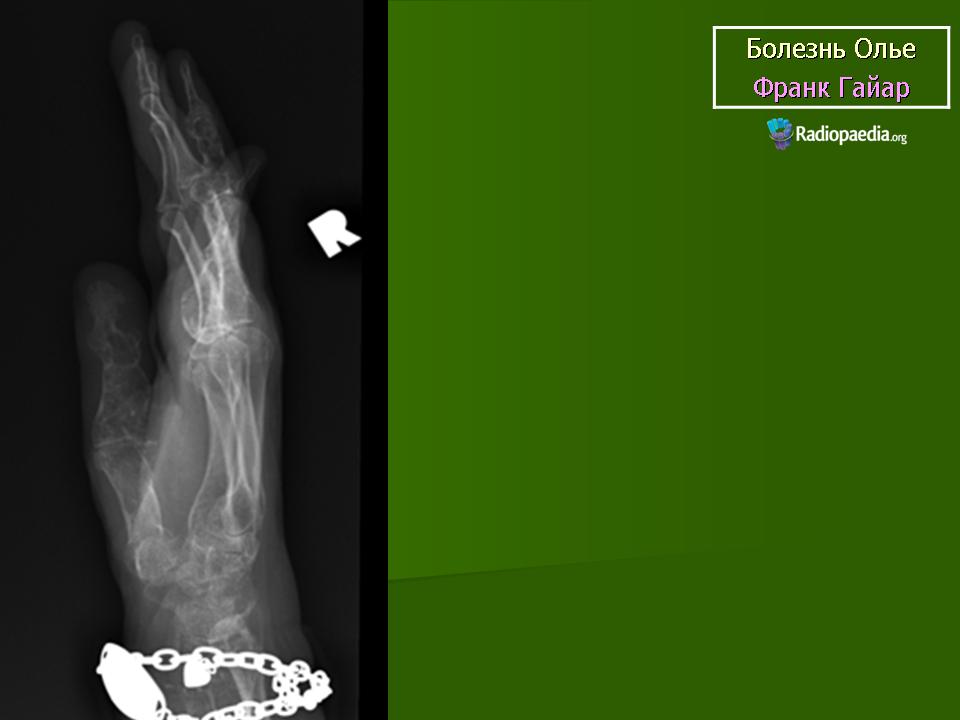

ОЛЛЬЕ СИНДРОМ (описан французским хирургом L. Ollier, 1830–1900; синоним – энхондроматоз, остеохондроматоз) – системное нарушение развития скелета, при котором на ранних этапах эмбриогенеза нарушается трансформация хряща в костную ткань; в растущей кости сохраняются очаги необызвествленной хрящевой ткани, что приводит к деформации и укорочению костей. Возможно поражение 1 (монооссальная форма заболевания), 2–3 (олигооссальная форма заболевания), 4 и более (полиоссальная форма заболевания) костей; поражаются преимущественно метафизы длинных трубчатых костей, фаланги пальцев, тазовые кости. Проявления заболевания возникают в возрасте 2–10 лет и зависят от локализации и тяжести процесса. Изменения обычно двусторонние, но асимметричные. При локализации процесса в нижних конечностях наблюдаются хромота, перекос таза, вальгусная или варусная деформация и прогрессирующее укорочение ног. При поражении верхних конечностей характерны лучевая или локтевая косорукость, выраженная деформация пальцев. Возможны патологические переломы. Нередко наблюдается малигнизация с развитием хондросаркомы. В редких случаях сочетается с гемангиомами мягких тканей (синдром Мафуччи). Диагноз уточняют при рентгенологическом исследовании, выявляющем четкие очаги овального или веерообразного просветления в метафизах длинных трубчатых костей. Тип наследования – предположительно аутосомно-доминантный. Лечение: выравнивание длины нижних конечностей с помощью ортопедической обуви, в случае выраженных деформаций показана хирургическая коррекция.

Клиническая картина. Заболевание выявляется в раннем детском возрасте, с началом ходьбы появляются деформации костей, хромота, прогрессирующее укорочение конечностей. Нередко первым проявлением болезни служат патологические переломы измененной кости; гемангиомы (при синдроме Мафуччи).Рентгенологически трубчатые кости умеренно или значительно укорочены, эпиметафизы булавовидно расширены, вздуты; в метафизах определяются очаги просветления неоднородной структуры.

Болезнь Олье.

Клиническая картина. Заболевание выявляется в раннем детском возрасте, с началом ходьбы появляются деформации костей, хромота, прогрессирующее укорочение конечностей. Нередко первым проявлением болезни служат патологические переломы измененной кости; гемангиомы (при синдроме Мафуччи). Рентгенологически трубчатые кости умеренно или значительно укорочены, эпиметафизы булавовидно расширены, вздуты; в метафизах определяются очаги просветления неоднородной структуры.